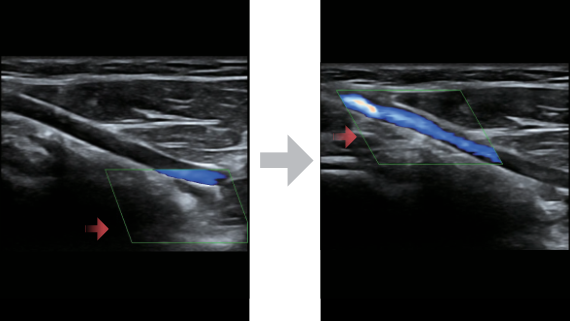

Based on the deep insights of customer needs, the DC-60 ECHO with X-Insight is designed to deliver high efficiency with precision imaging, which is empowered by eXpress Clarity, eXceptional Intelligence and eXceeding Experience.